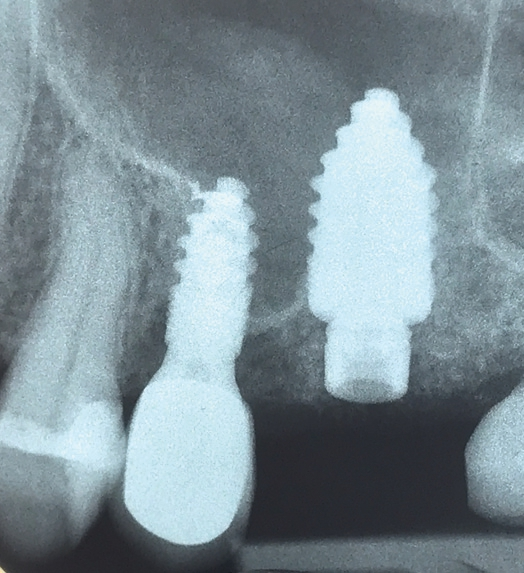

Widerwillig reifte in mir der unschöne Gedanke an einen Längsriss der palatinalen Wurzel des Zahnes 26. Die Beschwerden und der unauffällige Röntgenbefund ließen nur diese Diagnose schlüssig erscheinen. Ich wandte mich bezüglich einer erneuten Behandlung an Dr. Armin Nedjat. Nach Infiltrationsanästhesie, mittels MagicPen, entfernte Dr. Nedjat die Goldkrone. Er extrahierte den dreiwurzeligen Zahn und versuchte, in den vorhandenen Alveolarknochen, welcher durch die Trifurkation eingeschlossen war, zu implantieren. Der erfahrene Behandler benutzte zunächst den gelben konischen Dreikantbohrer. Danach erfolgte im D3- Knochen die Verdichtung des Knochens mit dem Ziel, eine Primärstabilität von 30–40 Ncm mit den Kondensern vom Durchmesser 2,4 mm, 3,0 mm, 3,8 mm, 4,3 mm zu erreichen. Nach dem Kondenser mit Durchmesser 5,3 mm war erst eine ausreichende Stabilität von 35 Ncm erzielt worden (Abb. 2). Minimalinvasiv wurde ein direkter Sinuslift durchgeführt – genial einfach durch Linkslauf des orangen Krestalbohrers vom Durchmesser 3,7 mm. Auf diese Weise kann die Schneider- Membran um bis zu 10 (!) mm angehoben werden. Ein Champions® (R)Evolution Titan-Implantat, Durchmesser 5,5 mm, Länge 10 mm, wurde inseriert (Abb. 3).

Nachdem der Behandler sämtliche Füllungs-, Wurzelfüllmaterialien sowie Zementreste von seiner Assistenz entfernen ließ, wurden die Zahnfragmente im Luftstrom der Multifunktionsspritze getrocknet und in den Champions Smart Grinder gegeben (Abb. 4). Nach wenigen Sekunden später war der Zahn zerkleinert. Es folgte eine 10-minütige Entkeimung und eine 3-minütige Neutralisation und das Augmentat war einsatzbereit. Es ließ sich sehr gut adaptieren, da es am Spatel leicht anhaftete. Autologer Dentingraft induziert nun Knochenwachstum (Abb. 5).

Glücklich verließ ich den Behandlungsstuhl, wohlwissend, welche Behandlung konventioneller Implantation mit externem Sinuslift und Einheilzeiten von bis zu einem Jahr mir erspart geblieben war. Seither bin ich begeisterter Anwender des Champions Smart Grinders. Die Abbildung 6 zeigt die Situation nach 12 Wochen.